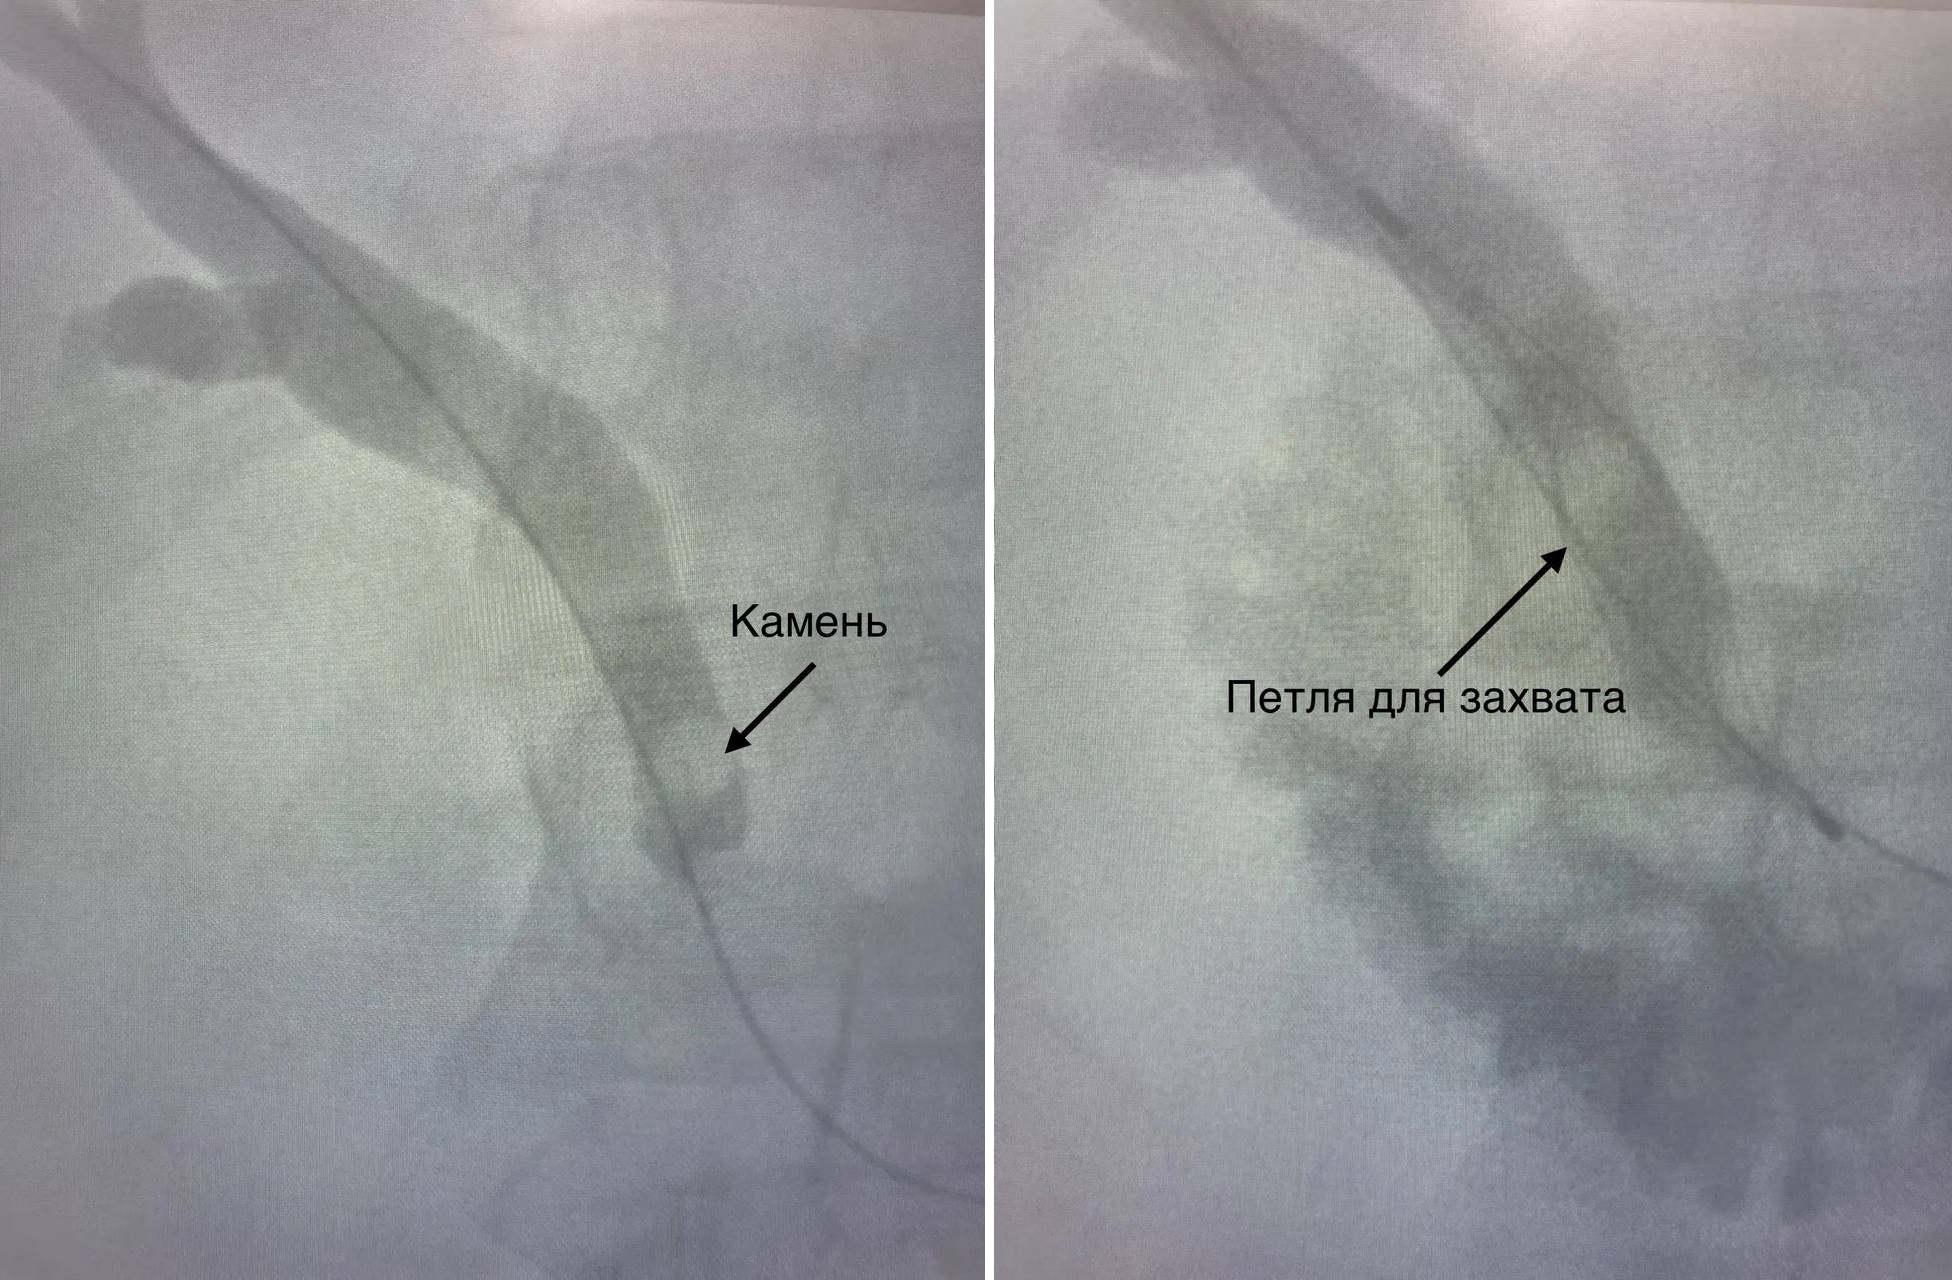

Однако врачи БСМП нашли другой выход. Под контролем рентгена хирурги провели миниинвазивную операцию. Через маленький разрез пациенту ввели проводник. А уже через него с помощью инструментов камень удалили.

«Через протоки печени мы ввели специальный инструмент в виде петли, захватили камень и достали его, используя жесткий тубус. Действовать нужно было аккуратно, просчитывая каждый миллиметр, в этом и была сложность. Подобную операцию мы проводили впервые, все прошло успешно. Пациент все время был в сознании, под местной анестезией», — поделилась рентгенхирург Зоя Антропова.